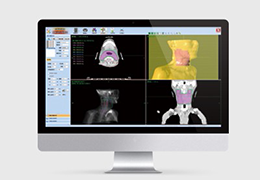

工作流智能。

在这里,先进的智能功能自动执行手动任务和工作流程步骤,以简化流程,提高技术人员工作效率,节省时间和金钱,并增强患者护理。

自动化设备定位和患者姿势确认可优化放射科技师的效率并加快工作流程。

自动技术选择可改善影像一致性并支持辐射剂量控制。

通过任务自动化功能改进感染控制,使放射科技师不再与潜在感染患者直接接触。